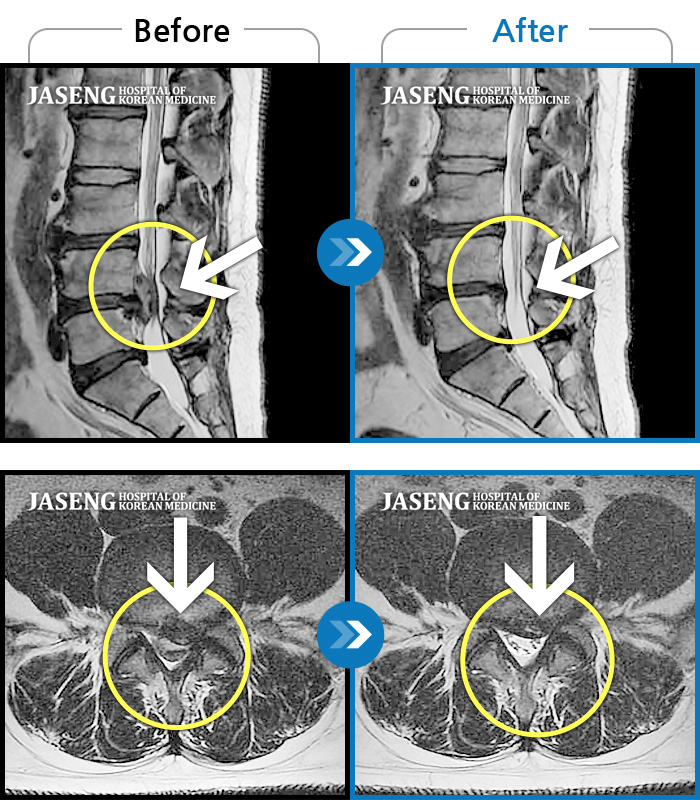

허리디스크

수원 · 김태성 원장

허리 통증과 좌측 대퇴부 저림과 당김

촬영시기

2023.02.03 ~ 2024.02.14

2024.11.21